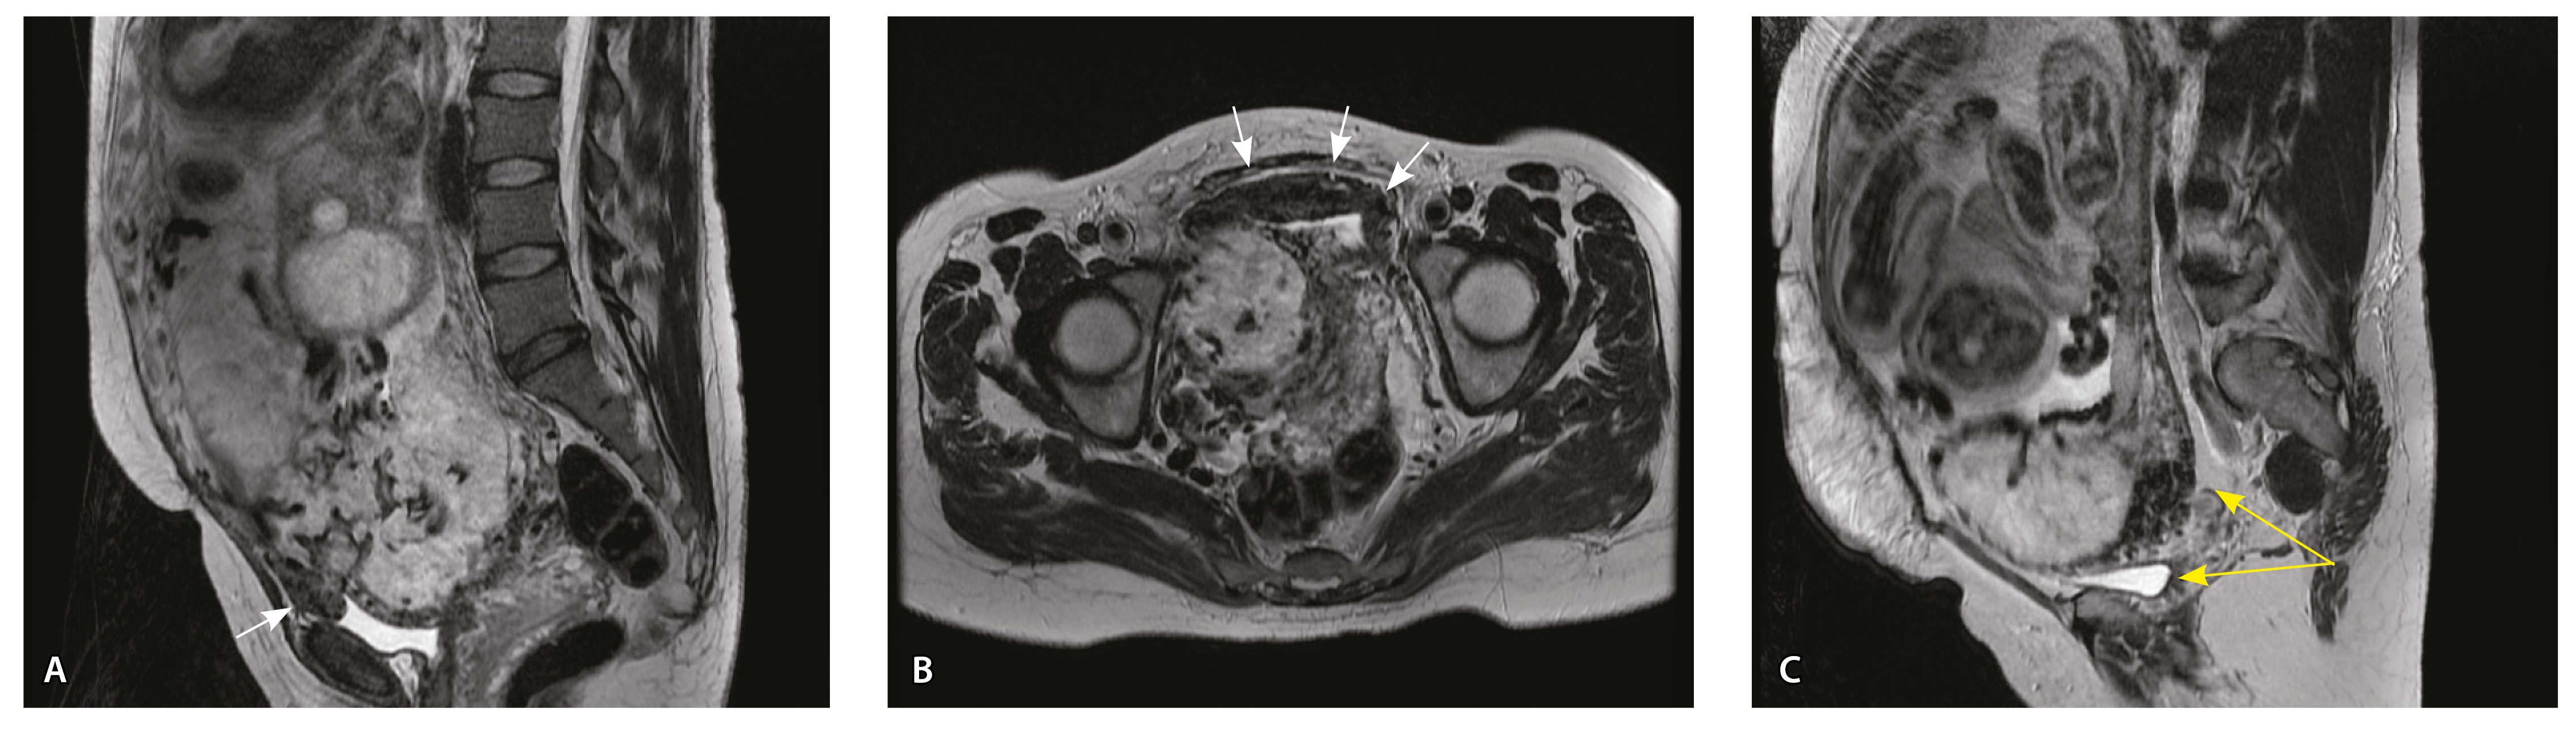

Сосуды 3-го типа. Внутриматочная гиперваскуляризация с дефицитом толщины миометрия, преимущественно сосуды срединного слоя, аналог pl. increta PAS 2, гестационная перестройка радиальных артерий (рис. 7).

Рис. 7. Беременность 34 недели, pl. increta, PAS 2 по FIGO. На магнитно-резонансных томограммах в режиме Т2-взвешенного изображения в сагиттальной (A, Б) и фронтальной (В) плоскостях определяется внутриматочная гиперваскуляризация с наличием многочисленных сливающихся сосудов в толще стенки матки, в области плацентарной площадки (белые стрелки); в нижнем маточном сегменте – выраженное истончение стенки матки, рубца от кесарева сечения с формированием маточной грыжи (желтые стрелки)

При pl. increta наличие патологических сосудов на изображениях МРТ связано с неполной гестационной перестройкой радиальных артерий, расположенных в срединном слое миометрия. Так, при окраске по Маллори они определяются как сжатые комплексы артерий среднего калибра, с частичным замещением внутренних слоев стенки матки, темно-красными фрагментами плодного фибриноида. На серийных срезах видно, что в этой артерии присутствует достаточное количество инвазивного цитотрофобласта (маркер цитокератин 8), но предыдущий срез подтверждает замещение мышечной оболочки фиброзной тканью как в стенке радиальной артерии, так и в периартериальном пространстве (рис. 8).